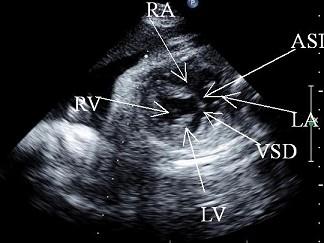

问题 胎儿心脏超声检查如图,最可能的诊断是 ( )

选项 A、心内膜垫缺损 B、大动脉换位(TGA) C、右心发育不良综合征 D、左心发育不良综合征 E、法鲁四联征

答案 A